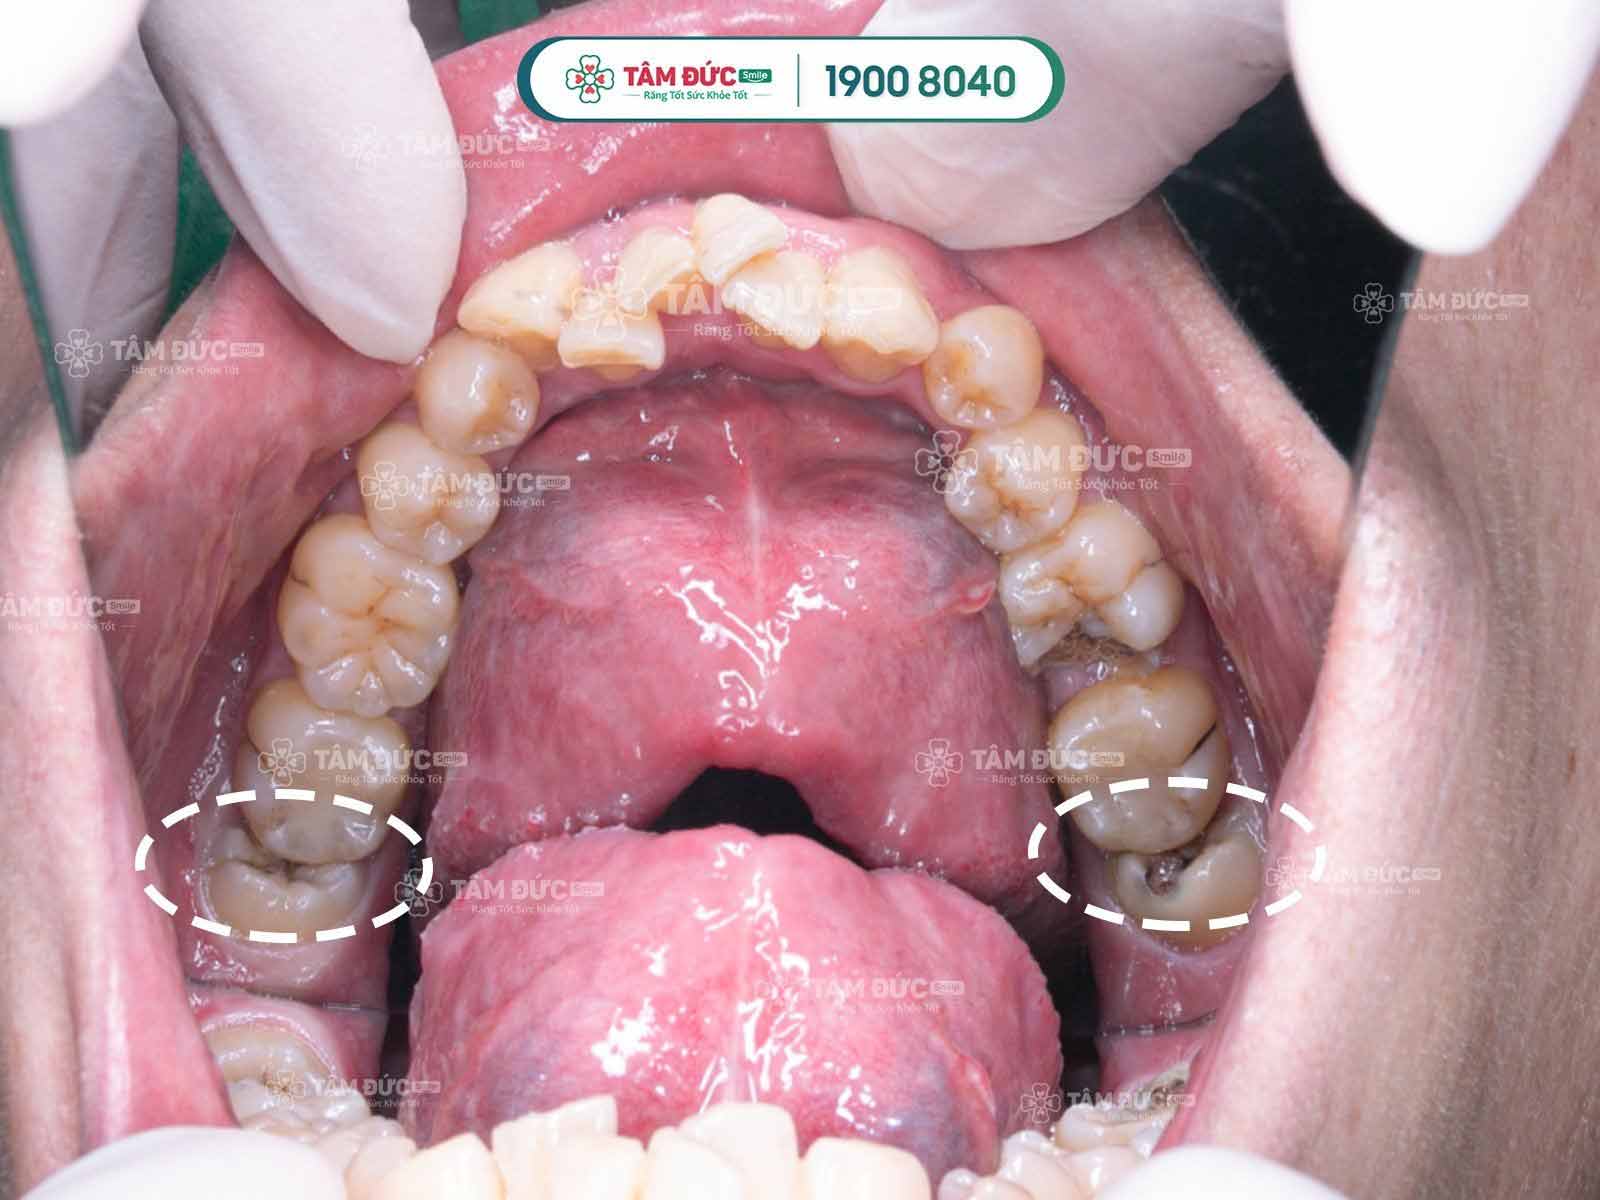

Do nằm ở vị trí khó vệ sinh nên dễ dàng xảy ra tình trạng sâu răng khôn.

Khi răng khôn mọc lệch và nghiêng về phía răng bên cạnh làm răng bị tổn thương, dễ gây gãy, vỡ, nứt.

Sâu răng khôn

Khi răng khôn mọc lệch, mọc ngầm trong thời gian dài sẽ tạo ra lực đẩy lớn, tác động đến những chiếc răng khác làm răng toàn hàm di chuyển và xô lệch. Điều đó không những làm mất đi tính thẩm mỹ của hàm răng mà còn bị sai khớp cắn, hàm trên và hàm dưới không khớp với nhau. Các trường hợp răng khôn mọc lệch, mọc ngầm được bác sĩ khuyến cáo nên nhổ bỏ càng sớm càng tốt tránh những biến chứng về sau.